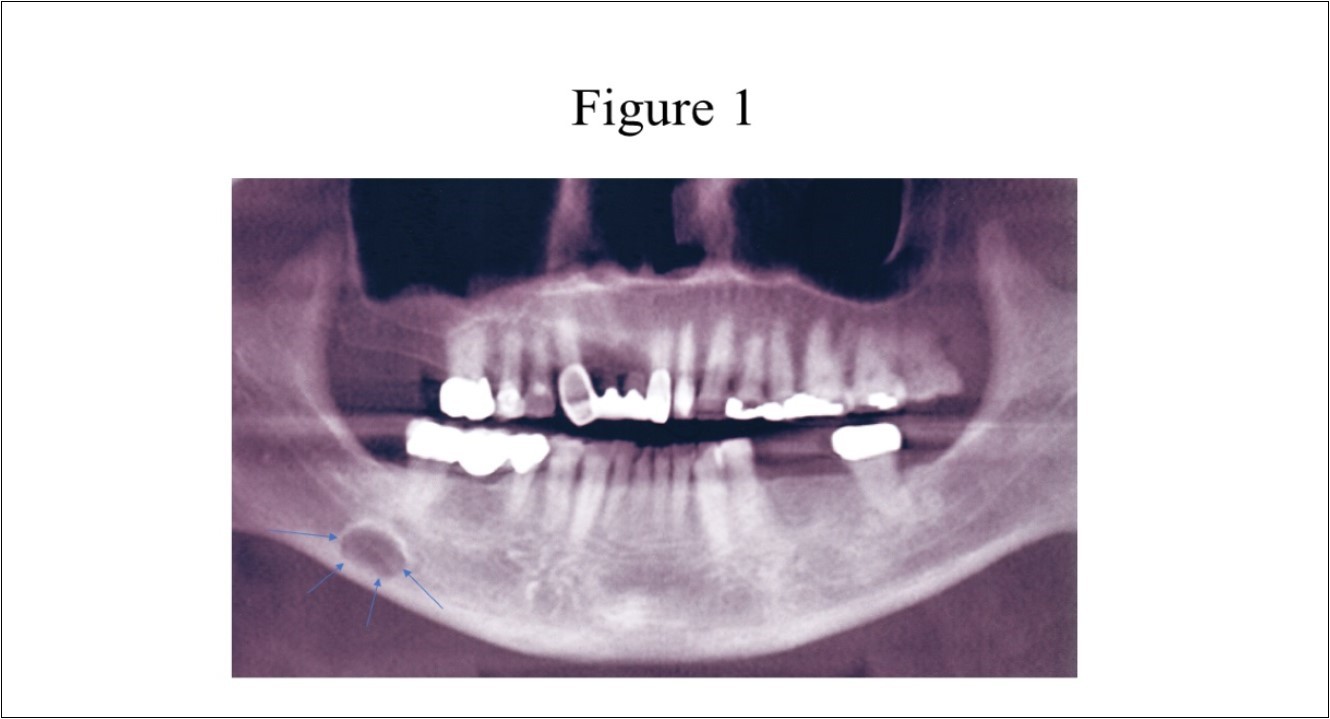

Radiographic features (Figure 1) of the SBC are a well-circumscribed unilocular, round or elliptical shaped radiolucency in the posterior mandible that are approximately 10 to 30mm in length. 1,3,4The radiographic lesion is often incidentally discovered when the patient completes a routine panoramic radiograph at the dentist office and does create concern for the dentist as it can mimic a cystic lesion.3,5,6

Figure 1.Panoramic radiograph of classically described SBC of the right posterior mandible illustrates the well-defined unilocular radiolucency in the right posterior mandible between the inferior alveolar canal and the inferior border of the mandible (arrows).

Panoramic radiograph of classically described SBC of the right posterior              mandible illustrates the well-defined unilocular radiolucency in the right posterior                mandible between the inferior alveolar canal and the inferior border of the mandible (arrows).